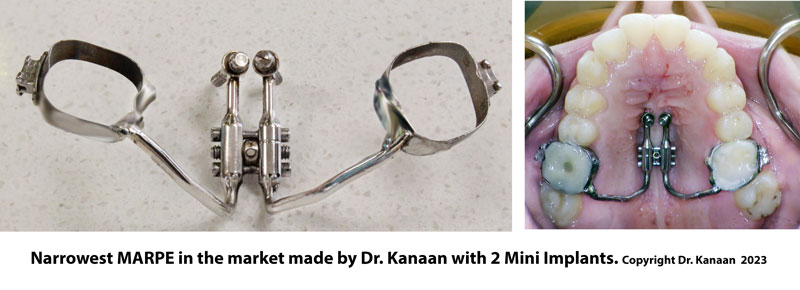

In 2014, Dr. Moon modified the traditional palatal expansion appliance to support 4 mini implants. This modification allowed the RPE to be attached directly to the bone thus transferring the expansion forces directly to the skeletal bone. He named his device Surgical Maxillary Expander SME. Sometimes, this concept is also referred to as the Mini screw-Assisted Rapid Palatal Expansion technique (MARPE) or Maxillary Skeletal Expander MSE.

Dr. Kanaan redesigned the SME to fit narrower palates with a safety release mechanism. He filed his invention with the United States Patent Office on Oct 10th, 2016 under Application US15/333,531 “Safety release orthodontic skeletal expander using mini-implants” (REF).

His expander comes in two sizes: 7 mm and 9 mm. However, in extremely narrow cases, Dr. Kanaan will custom-make a surgical expander to fit the patient's mouth. A cone-beam computed tomography might need to measure the exact width of the maxilla.

What are the benefits of using mini-implants with the expander?

- The mini implants will transfer the force to the bone directly, resulting in better skeletal expansion.

- Less force is transferred to the supporting teeth. This is important in cases with weak teeth.

- The 4 implants will support the expander in place. This is beneficial in Invisalign cases or cases where posterior teeth are missing.

Dr. Kanaan made her a custom-made MSE using only a 2-screw narrow MSE. Dr. Kanaan was not satisfied with the width after stage one and decided to do a second stage to get further expansion and enhance her breathing. The final results were magnificent, and the patient was extremely pleased with her functional, breathing, and cosmetic results.